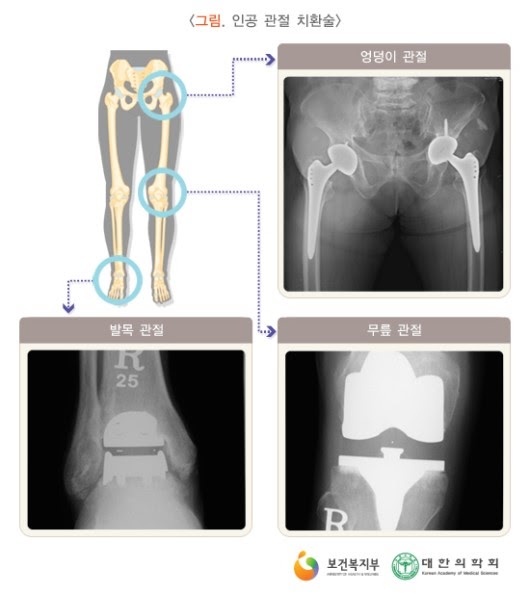

보다 심한 관절염에서 고려되는 방법으로, 인공 관절 치환술이 대표적이고 효과적인 방법입니다. 손목이나 발목 관절의 퇴행성 관절염에 대해서는 경우에 따라 관절 고정술이나 자가 조직을 이용한 관절 성형술이 고려되기도 합니다.*마모와 파손, 감염, 해리, 불안정성 등의 합병증으로 인공관절은 수명이 있을 수 밖에 없고, 재치환술은 피할 수 없습니다. 인공관절 재치환술은 수술 술기도 어려울 뿐만 아니라 그 결과도 일차 치환술에 비하여 떨어지는 한계가 있습니다.

:관절경을 이용한 관절 내 유리체의 제거, 활막 절제술, 골극 제거술, 절골술, 관절 성형술 및 관절 고정술 등